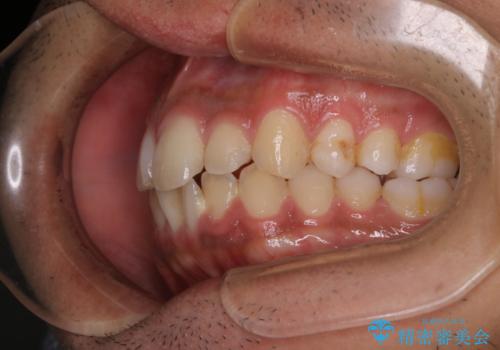

矯正をスタートする前にクリーニングを行いました。PMTC60分コースを行いました。

10年ぶりのクリーニングのため着色や歯石、プラークの量は多めでした。